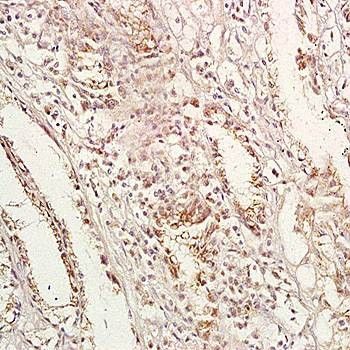

- IHC-P analysis of human gastric carcinoma tissue using GPA33 antibody at a dilution of 1:200.